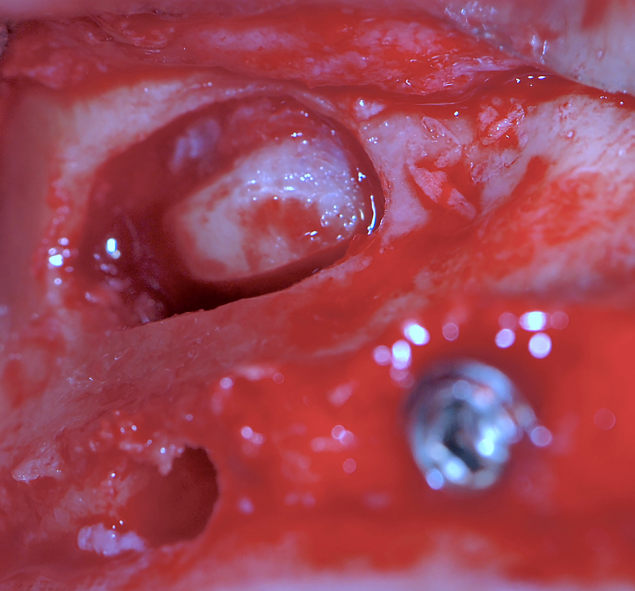

Dopo la rimozione dei denti residui e degli impianti, il paziente è stato immediatamente riabilitato con due protesi totali rimovibili diagnostiche in RP, che hanno migliorato i rapporti intermascellari, la VDO, OB, OJ, fonetica ed estetica. È stato eseguito un tracciato cefalometrico su una radiografia laterale del cranio per una valutazione funzionale iniziale del caso, seguita da una pianificazione protesica virtuale (Fig. 4), quindi radiologica (Fig. 5) e chirurgica. Le caratteristiche delle protesi studiate hanno determinato la pianificazione chirurgica (Smop, SwissMeda) (Fig. 6) e due guide chirurgiche sono state successivamente sinterizzate al laser (2Ingis) (Fig. 7). Gli impianti sono stati quindi posizionati come programmato (Figg. 8, 9), ad eccezione di quelli ai mascellari posteriori, dove è stato eseguito bilateralmente un grande rialzo del seno mascellare (Fig. 10).

Dopo alcuni mesi, altri quattro impianti sono stati inseriti ai mascellari posteriori utilizzando la stessa guida chirurgica (Fig. 23), e dopo altri sei mesi l’arcata superiore era pronta per essere caricata con una riabilitazione protesica fissa su impianti. Tutte le procedure dell’arcata inferiore sono state ripetute per l’arcata superiore (Figg. 24, 25), perfezionando l’ADSD e controllando l’accuratezza dei contatti occlusali.